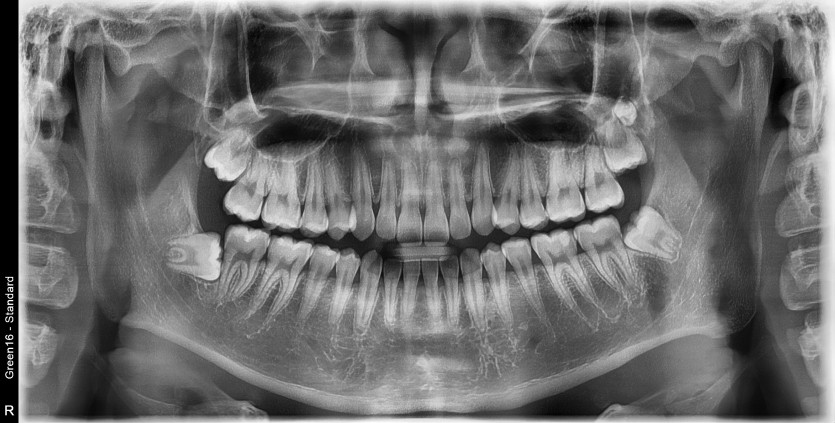

#28,29(과잉치),38 사랑니 발치

구강 외과 전문의가 당일 발치했습니다.